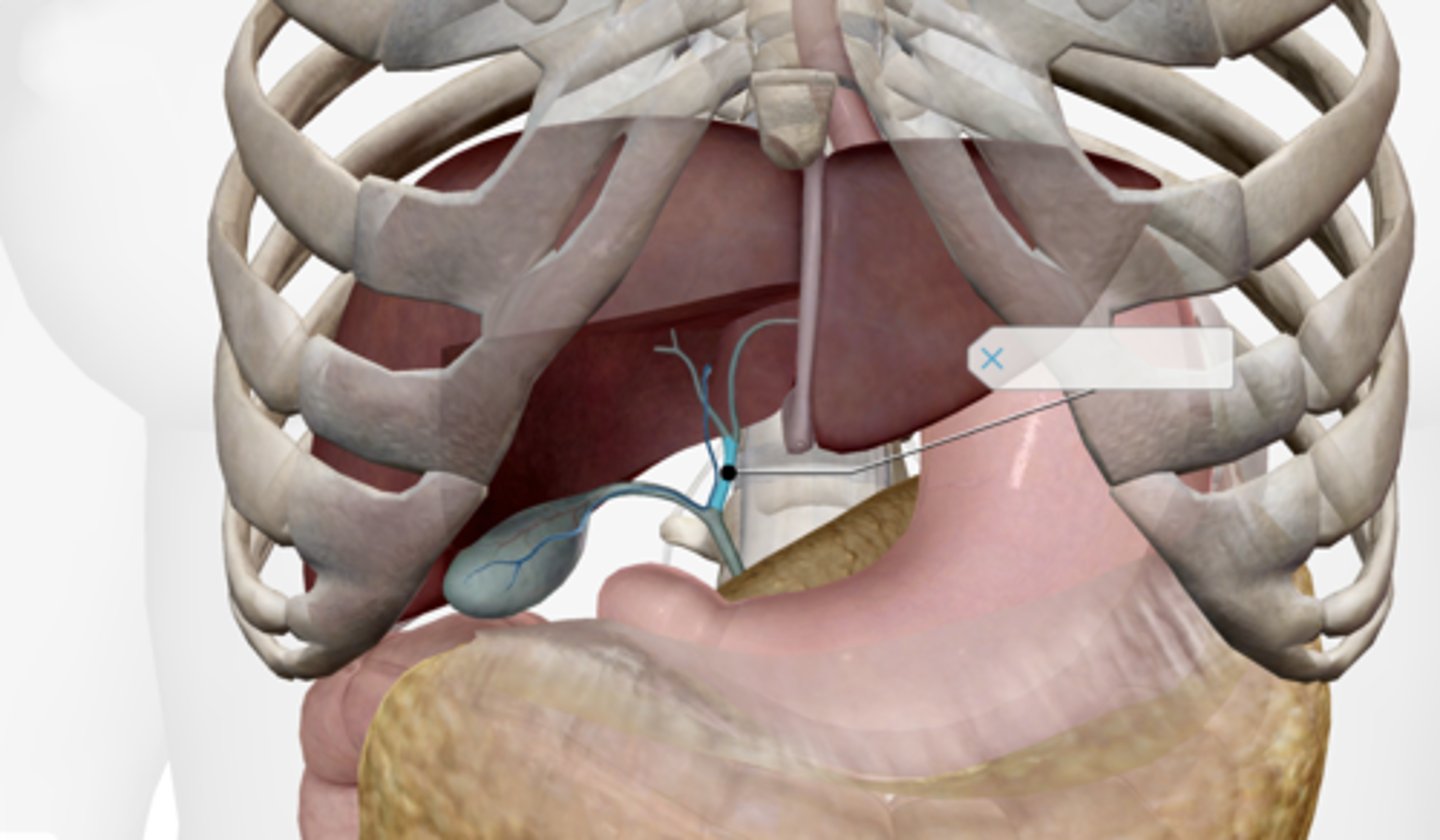

Gallbladder

Cystic duct

Common hepatic duct

Common bile duct

Pancreas

Main pancreatic duct (duct of Wirsung)

Accessory pancreatic duct (duct of Santorini)

Liver

Hepatic artery & vein

Falciform ligament

Duodenum

Duodenal papilla